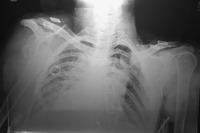

晚上10點多到接到台北叔叔電話, 問我看得出手臂肱骨有在正常位置嗎, 我說應該摸得出來, 過不久就帶桃園的嬸嬸還有堂姐過來, 看著嬸嬸穿著醫院的衣服過來, 手臂呈現紅衛兵舉起的45度角, 上不去也下不來,肩上畫著將開刀的黑色筆跡, 原來下午4點多就因車禍人飛出去, 整個左臂摔在地上,省桃判定一定要快開刀, 後來看了一間嬸嬸熟識的中醫整骨師, 但手始終無法上下活動, 後來跟台北開中藥行的叔叔一起過來, 看了X光片,肱骨沒裂沒斷,但錯位滿多的, 肱骨頭都快碰到肋骨了, 至今未處理過當天車禍錯位這麼多的, 處理一個多小時終於聽到叩,手能上下活動了, 不過車禍骨頭如果有傷到, 還是癒合三個月後再處理會比較恰當。 嬸嬸平常就有在做功德, 剛好在緊急時有媒介幫他處理好, 我想這一切就是緣的造化吧。